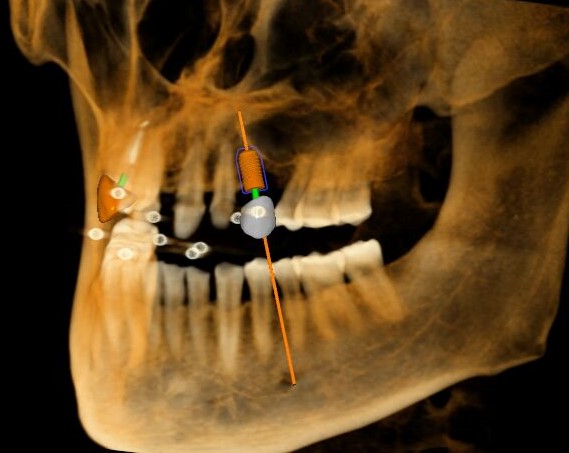

觀察患者CT,可看出患者有上頜竇粘膜囊腫,粘膜囊腫為竇內(nèi)腺體阻塞所致,視情況可有手術(shù)摘除和不予處理兩種方法,此次患者拒絕手術(shù)摘除,故需規(guī)避上頜竇位置。

※高精確度:采用紅外光學(xué)定位技術(shù),術(shù)中在患者前牙美學(xué)間隙兩側(cè)精確植入兩顆植體,并且完美避開(kāi)左側(cè)上頜竇囊腫;

※實(shí)時(shí)導(dǎo)航:輕松把控種植位點(diǎn)、角度、深度,與術(shù)前CBCT整合顯示在一起,實(shí)時(shí)引導(dǎo)手術(shù)進(jìn)行,同時(shí)可以實(shí)現(xiàn)手術(shù)器械的可視化與實(shí)時(shí)跟蹤。

三維視圖

根據(jù)患者CT顯示,使用種植導(dǎo)航軟件設(shè)術(shù)前手術(shù)方案??紤]到患者拒絕手術(shù)摘除上頜竇囊腫等因素,此次手術(shù)選用了Straumann骨水平4.10*8.0mm的植體,植體末端位點(diǎn)設(shè)計(jì)距上頜竇底壁2mm處的同時(shí)兼顧種植方向和修復(fù)間隙,來(lái)達(dá)到理想的效果。

導(dǎo)航下精細(xì)分配修復(fù)間隙,精細(xì)規(guī)劃植入方向,避開(kāi)上頜竇底,精確植入

從術(shù)后CBCT顯示可以看出,手術(shù)操作中完美地避開(kāi)上頜竇底,并兼顧了正確的種植方向和修復(fù)間隙